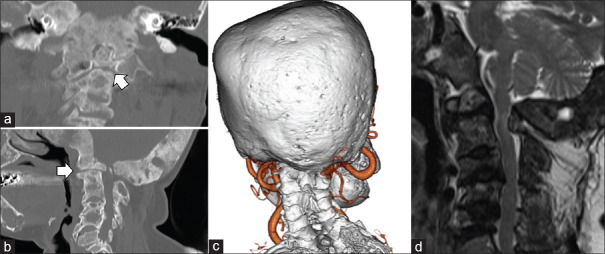

纤维发育不良(FD)是一种罕见的骨骼疾病,其特点是正常骨骼被纤维结缔组织取代,导致骨骼形成异常。本病例报告详细介绍了一名颅椎骨交界处纤维发育不良的 61 岁女性患者的成功治疗过程。该患者曾有颅内脑膜瘤病史,并已被诊断为 FD,在一次跌倒后出现步态障碍和肌肉无力。影像学检查显示,患者的颅骨和颈椎有广泛的多发性 FD 病变,C2 骨突骨折导致脊髓受压。患者接受了枕颈固定和减压手术。术中使用了 O 型臂导航,以确保准确放置螺钉和有效减压。该手术可以正确定位C2和C3椎弓根螺钉、切除增生的枕骨和C1后弓、放置枕骨钢板并避开囊肿组件。在两年的随访中,没有发现螺钉松动的迹象,患者的临床症状明显改善。该病例强调了量身定制的手术策略和先进导航技术在处理复杂 FD 病例,尤其是涉及 CVJ 的病例中的重要性。它还凸显了治疗多发性 FD 所面临的挑战,因为完全切除往往是不可行的。该病例的成功结果支持使用减压手术结合稳定术来缓解症状并预防进一步的并发症。

Fibrous dysplasia (FD) is a rare skeletal disorder characterized by the replacement of normal bone with fibrous connective tissue, leading to abnormal bone formation. This case report details the successful treatment of a 61-year-old woman with FD at the craniovertebral junction (CVJ). The patient, who had a history of intracranial meningioma and had already been diagnosed with FD, experienced worsening gait disturbance and muscle weakness following a fall. Imaging studies revealed extensive polyostotic FD lesions in the skull and cervical spine, along with a C2 odontoid fracture causing spinal cord compression. The patient underwent occipitocervical fixation and decompression surgery. Intraoperative O-arm navigation was used to ensure accurate screw placement and effective decompression. This procedure allowed for proper positioning of the C2 and C3 pedicle screws, resection of the hyperplastic occipital bone and C1 posterior arch, and placement of the occipital plate with avoiding the cyst components. At a 2-year follow-up, there were no signs of screw loosening, and the patient showed marked clinical improvement. This case emphasizes the importance of tailored surgical strategies and the use of advanced navigational technologies in managing complex FD cases, particularly those involving the CVJ. It also highlights the challenges of treating polyostotic FD, where complete resection is often unfeasible. The successful outcome in this case supports the use of decompressive surgery combined with stabilization to relieve symptoms and prevent further complications.